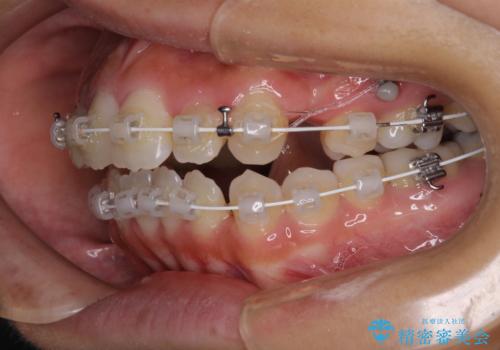

開咬と前突を改善 ワイヤー装置での抜歯矯正

- 矯正装置

- 審美装置

- 口元の突出感と開咬を気にして来院された患者様です。

口元の突出感を改善するため、第一小臼歯を抜歯して口元を引っ込めることとしました。

一般的には上下左右の第一小臼歯4本を抜歯しますが、下顎に対して上顎が前方に位置しているため、まずは上顎小臼歯2本を抜歯し、治療経過を見て下顎小臼歯を抜歯するかどうかを決めていくこととしました。

元々むし歯の処置歯が多く、神経を取り除いている歯が多くありましたが、どうやら右上の前歯と小臼歯は外傷により神経を失った可能性があり、抜歯したスペース前後の歯が全く動かない状態でした。

結果として下顎の小臼歯は抜歯せず、右上の抜歯スペースはむし歯処置を兼ねてオールセラミックブリッジにて補綴治療を行うこととしました。

動かない歯での停滞や、出産と子育てなどにより治療期間は長期化しましたが、整った歯列にて仕上げることができました。